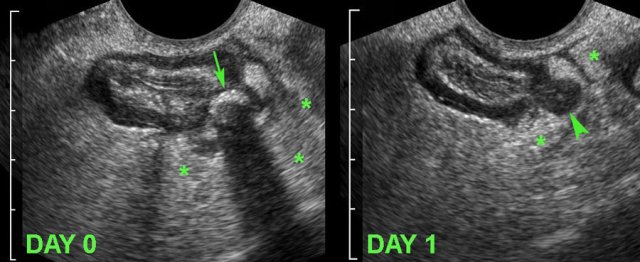

Uncomplicated course of sigmoid diverticulitis documented by TVUS. Uncomplicated course of sigmoid diverticulitis documented by TVUS.

Diverticulitis

A 34-year old woman, presented with acute LLQ pain.

TVUS demonstrated local wall thickening of the sigmoid and a diverticulum harbouring a fecolith (arrow), which was surrounded by inflamed fat (*), representing mesentery and omentum, effectively walling-off the imminent perforation.

The next day, she felt much better and follow up TVUS showed a hypoechoic, oedematously thickened, empty diverticulum (arrowhead).

The fecolith apparently did evacuate to the sigmoid lumen.